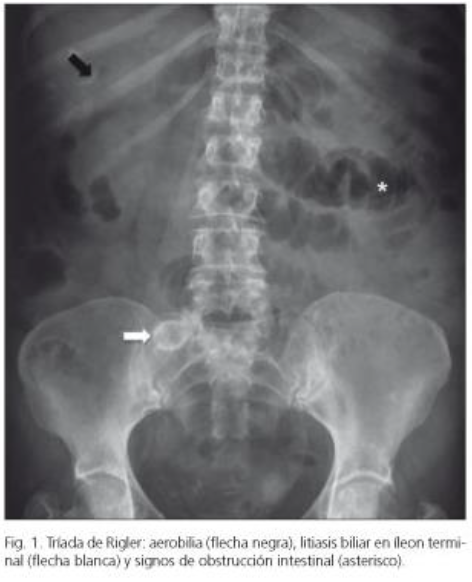

Íleo Biliar - Clínica y Tríada de Rigler

A

Rx Patognomonico (Tríada de Rigler):

1. Aerobilia (aire alrededor de vesicula)

1. Obstruccion intestinal

1. Calculo en situacion aberrante